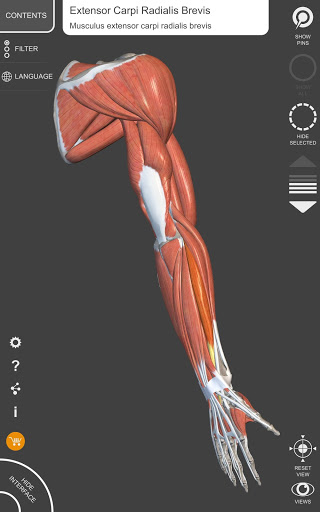

"Anatomía - Atlas 3D" permite estudiar la anatomía humana de forma fácil e interactiva.

A través de una interfaz sencilla e intuitiva es posible observar cada estructura anatómica desde cualquier ángulo.

Los modelos anatómicos 3D son especialmente detallados y con texturas de hasta una resolución de 4k.

La subdivisión por regiones y las vistas predefinidas facilitan la observación y el estudio de partes individuales o grupos de sistemas y las relaciones entre los diferentes órganos.

MODELOS ANATÓMICOS 3D

• Sistema musculoesquelético

nervioso • Sistema respiratorio • Sistema digestivo • Sistema urogenital (masculino y femenino) • Sistema endocrino • Sistema linfático • Sistema ocular y auditivo CARACTERÍSTICAS • Interfaz sencilla e intuitiva • Rotar y hacer zoom en cada modelo en el espacio 3D • Opción para ocultar o aislar uno o varios modelos seleccionados • Filtro para ocultar o mostrar cada sistema • Función de búsqueda para encontrar fácilmente cada parte anatómica • Función de marcador para guardar vistas personalizadas • Rotación inteligente que mueve el centro de rotación automáticamente • Función de transparencia • Visualización de músculos a través de niveles de capas desde las superficiales hasta las más profundas • Al seleccionar un modelo o un pin, aparece el término anatómico relacionado • Descripción de los músculos: origen, inserción, inervación y acción • Mostrar/ocultar interfaz de usuario (muy útil con pantallas pequeñas) MULTILINGÜE • Los términos anatómicos y la interfaz de usuario están disponibles en 11 idiomas: latín, inglés, francés, alemán, italiano, portugués, turco, ruso, español, Chino, japonés y coreano • Los términos anatómicos se pueden mostrar en dos idiomas simultáneamente REQUISITOS DEL SISTEMA • Android 8.0 o posterior, dispositivos con al menos 3 GB de RAM Reversi